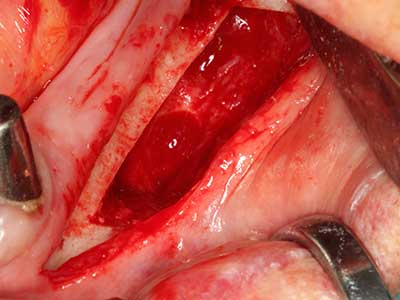

Piezosurgery has additional advantages when harvesting bone blocks. In addition to the high precision with osteotomy described above, the use of the thin saw tips specifically minimizes loss of material. Greater loss of material during harvesting can be expected with the thicker instrument tips, particularly when using Lindemann drills (Lakshmiganthan, Gokulanathan et al. 2012). The basal separation, which is necessary particularly for retromolar block transplants, is simplified by specially designed rectangular saws, with the result that piezosurgery is viewed as a precise, simple and safe procedure for harvesting retromolar bone blocks (Happe 2007) (Fig. 1-12).

Indication: Bone splitting

Bone tissue is not simply a mineral structure but also contains a substantial proportion of collagen fibres. This means it not only has good compressive strength but also a degree of flexibility, which can be taken advantage of when performing bone augmentations. In the classical expansion procedure using bone splitting, the atrophied alveolar ridge is split longitudinally and carefully expanded after reaching an adequate osteotomy depth (Fig. 13-16), ideally without substantial removal of the periosteum (Brugnami, Caiazzo et al. 2014, Stricker, Fleiner et al. 2014). Screw and plate systems with increasing expansion distance have proven effective in separating the two bone lamellae while remaining below the fracture threshold. In general, residual bone widths of at least 3–4 mm are required (Chiapasco, Zaniboni et al. 2006) to guarantee adequate flexibility and sufficient bone coverage of the future implants. If necessary, a vertical relief osteotomy on one or both sides can improve flexibility. A combination with additional augmentation techniques, particularly on the buccal side, has been described as an alternative to the classical technique.

The splitting procedure is particularly atraumatic and there is no significant loss of dimension when using piezosaws, and there are no significant differences between implants in split jaws and implants in an alveolar ridge without a bone deficit (Chiapasco, Zaniboni et al. 2006, Danza, Guidi et al. 2009). However, sufficient continuous irrigation is essential, particularly with locally restricted and deep splitting to prevent thermal stress in the apical osteotomy regions.